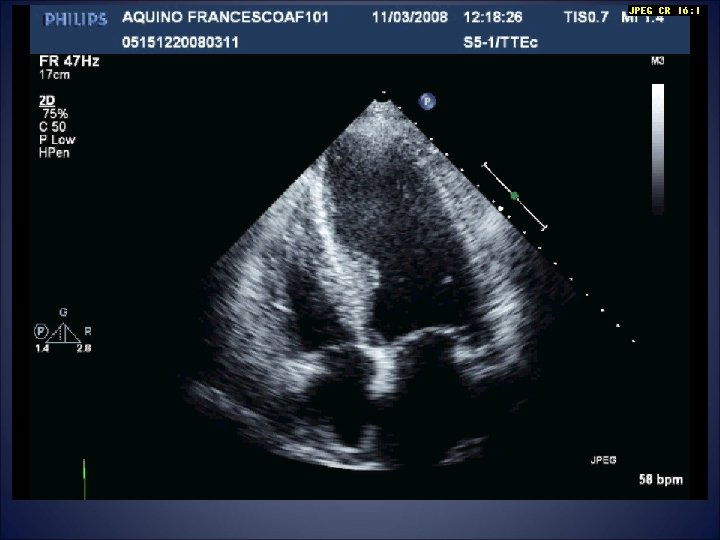

Acute HF hospitalization 13/08/2008 • Raised jugular venous pressure • Pulmonary oedema • Aortic

Acute HF hospitalization 13/08/2008 • Raised jugular venous pressure • Pulmonary oedema • Aortic valve stenosis

Cardiac MRI • The myocardium is thinned at the apical level with a diffuse

Cardiac MRI • The myocardium is thinned at the apical level with a diffuse delayed enhancement and moderately dyskinetic movement during the ventricular contraction • Fibrotic and non-viable tissue